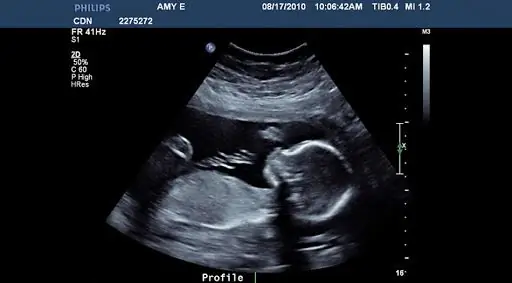

В штате Теннесси будет принят новый закон, предоставляющий еще не рожденным детям одни из наилучших условий защиты в Соединенных Штатах. Сенат штата Теннесси подавляющим большинством голосов проголосовал за принятие закона, запрещающего аборты после обнаружения сердцебиения плода. Обычно это около шести недель беременности.